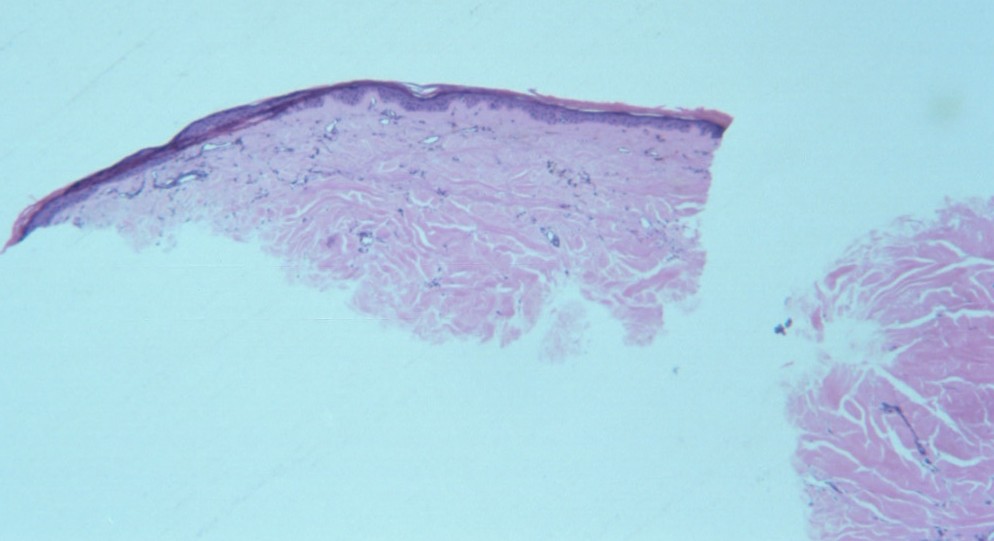

macular-amyloidosis